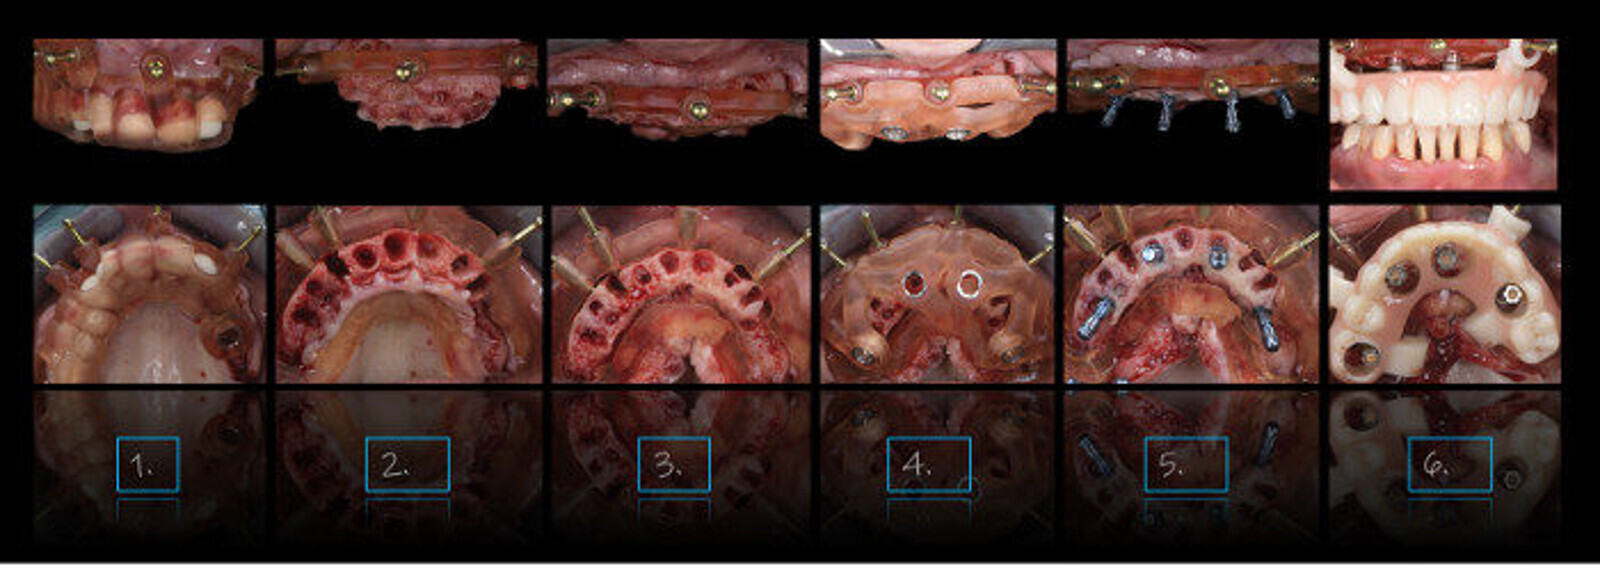

Full-arch Smile in a Box system. (Image: Ricardo Mitrani)

You will also review the treatment planning service Straumann Smile in a Box. To what extent can this support dental practices in treating patients?

The Smile in a Box concept has numerous attributes that can enhance the patient’s treatment experience. It allows the treating team to review and discuss the multiple steps that the therapy involves in-depth. It also ensures that all the parts and pieces needed to carry out these procedures are carefully selected and ordered, including a CAD/CAM-generated provisional restoration. It therefore is a quite pragmatic addition to our interdisciplinary collection of resources.